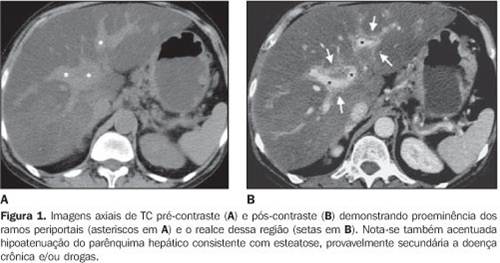

Radiologia:

lesão celular 03-esteatose hepática

http://www.scielo.br/scielo.php?pid=S0100-39842008000200015&script=sci_arttext